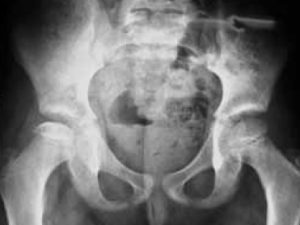

Douleur de hanche de l’enfant

Quels diagnostics ? La sémiologie d’une douleur de hanche de l’enfant est représentée par une boiterie. Ce symptôme (hors d’un contexte traumatique) est un motif fréquent de consultation en milieu…